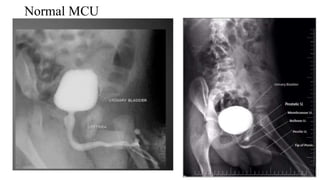

Normal MCU

Imaging in MCU